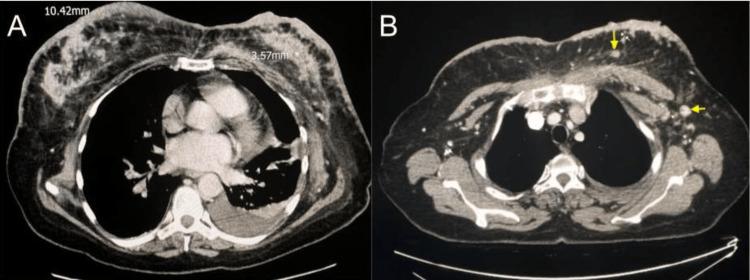

Inflammatory breast cancer (IBC) is a rare and aggressive form of breast cancer that accounts for only a small percent of invasive breast cancers in the United States. We report a case of advanced bilateral IBC in a 60-year-old female. This case report explores the clinical presentation, pathological findings, and different imaging modalities that can assist in the diagnosis of this disease. The initial diagnosis was based on imaging findings from both contrast-enhanced computed tomography (CECT) and positron emission tomography-computed tomography (PET-CT). The diagnosis was then confirmed with histopathological findings.

炎性乳腺癌(IBC)是一种罕见且侵袭性强的乳腺癌形式,在美国仅占浸润性乳腺癌的一小部分。我们报告一例60岁女性的晚期双侧炎性乳腺癌病例。本病例报告探讨了有助于诊断该疾病的临床表现、病理结果及不同影像学检查方法。初步诊断基于对比增强计算机断层扫描(CECT)和正电子发射断层扫描-计算机断层扫描(PET-CT)的影像学结果。随后通过组织病理学结果确诊。